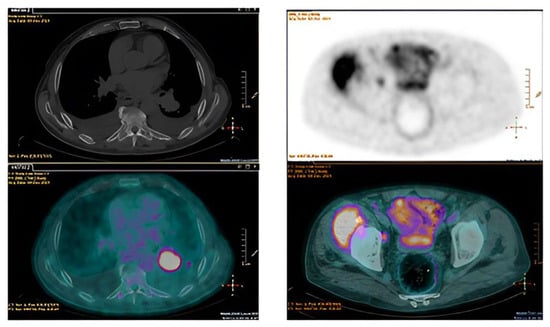

- The fundamental role of multimodality imaging (TTE + TEE, brain MRI, 18F-FDG/PET–CT scan) for NBTE diagnosis;

- The role of 2D and 3D-TEE for detection and characterization of NBTE valvular lesions;